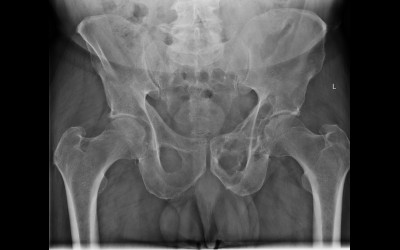

Röntgenfall des Monats April 2017 mit Auflösung

76 jähriger Patient mit diffusen Skelettschmerzen

Keine Grunderkankung bekannt, kein Trauma.